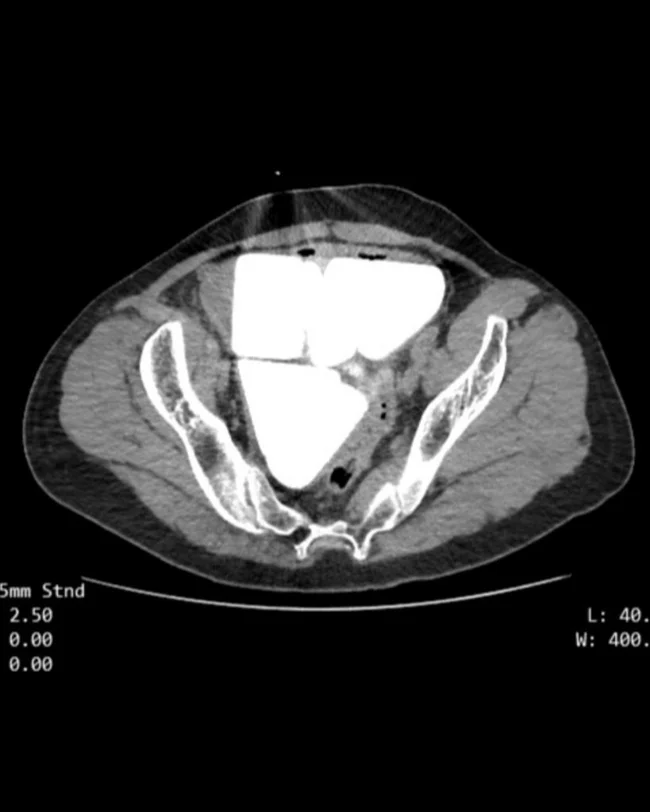

The man was sent for diagnostics to check the cause of his complaints. Despite the fact that he had no symptoms of pain, fever or infection, doctors performed an ultrasound examination (ultrasound) and what they saw on the images shocked specialists.

It turned out that the man's bladder contained giant stones in equal geometric proportions. Of the six stones, one was cube-shaped, and five were in the shape of an equilateral pyramid.

The man was immediately hospitalized, and then underwent a successful operation. During the intervention, surgeons discovered that the length of the side of the cubic stone was 7 cm on all sides, and the edges of the pyramid were 6 cm long, and the total mass of the stone was more than 2 kg.